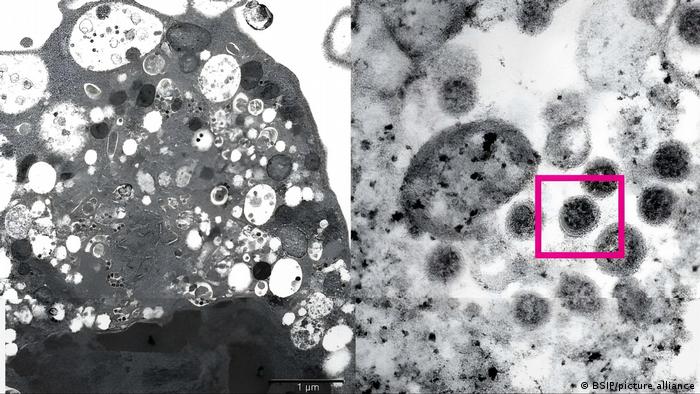

La subvariante BA.2 de la variante del coronavirus ómicron, que se ha impuesto rápidamente en Dinamarca, es más transmisible que la más común BA.1 y más capaz de infectar a las personas vacunadas, según un estudio danés.

El estudio, que analizó las infecciones por coronavirus en más de 8.500 hogares daneses entre diciembre y enero, descubrió que las personas infectadas con la subvariante BA.2 tenían aproximadamente un 33 % más de probabilidades de infectar a otras, en comparación con las infectadas con BA.1.

En todo el mundo, la subvariante "original" BA.1 representa más del 98 % de los casos de ómicron, pero su prima cercana BA.2 se ha convertido rápidamente en la cepa dominante en Dinamarca, destronando a la BA.1 en la segunda semana de enero.

"Concluimos que la BA.2 de ómicron es intrínsecamente más transmisible que la BA.1, y que además posee propiedades inmunoevasivas que reducen aún más el efecto protector de la vacunación contra la infección", señalan los investigadores del estudio.

"Si ha estado expuesto a ómicron BA.2 en su hogar, tiene un 39 % de probabilidades de infectarse en siete días. Si en cambio has estado expuesto a BA.1, la probabilidad es del 29 %", declaró a Reuters el autor principal del estudio, Frederik Plesner. Esto sugiere que la BA.2 es un 33 % más infecciosa que la BA.1, añadió.